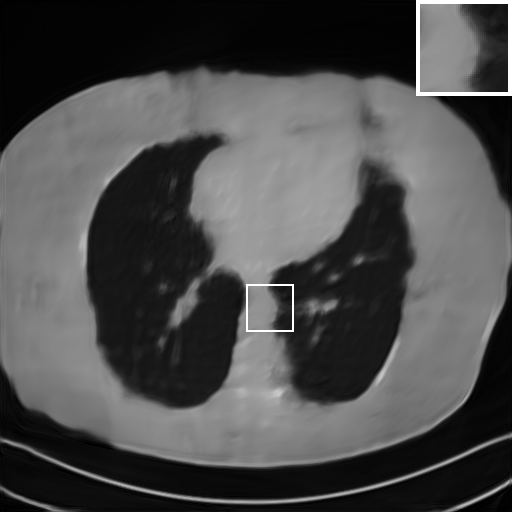

We further increase the noise level contained in the raw data to 10% white Gaussian noises and list the quantitative results in Table IV. It can be observed that the reconstruction performance of the TV model is poor in the case of high-level noises with PSNR dropping by 4 to 5 dB compared to the previous experiments. On the other hand, the performance of the learning-based methods is less sensitive to noises. The SIPID method relying on the sinogram interpolation works better than FBP-Unet. And the deep unrolling methods (i.e., PD-net, IFSR-net, SFSR-net) outperform the traditional iterative algorithm when the scanning range is limited and data is corrupted by noises. Similar to the previous experiments, compared with other deep learning algorithms, our LRIP-nets give the reconstruction results with higher PSNR and SSIM. Moreover, the low-resolution image obtained by the projection data down-sampled with rate 1/8 always gives the best reconstruction results with more than 2 dB PSNR and 0.05 SSIM increments compared to the PD-net. Fig. 6 illustrates the reconstructed images from different methodologies with scanning angular range of and 10% Gaussian noises. It can be seen that the both TV model and the FBP-Unet suffers from significant artifacts, which present distortions in the angular range of the missing scan. Other learning-based methods provides better visual qualities than FBP-Unet, and our LRIP-net1/8 still gives the best reconstruction result with correct boundaries and fine structures.